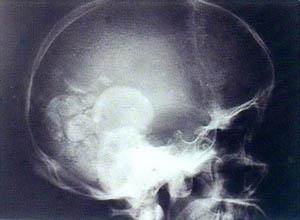

简介脑肺吸虫病是肺吸虫成虫寄生于脑内并不断移行造成的机械性损伤,及其代谢物等引起的免疫病理反应的一种疾病,以颞叶最常受损。本病临床表现有头晕,头痛,癫痫,偏瘫,视力障碍等,伴全身症状发热等。